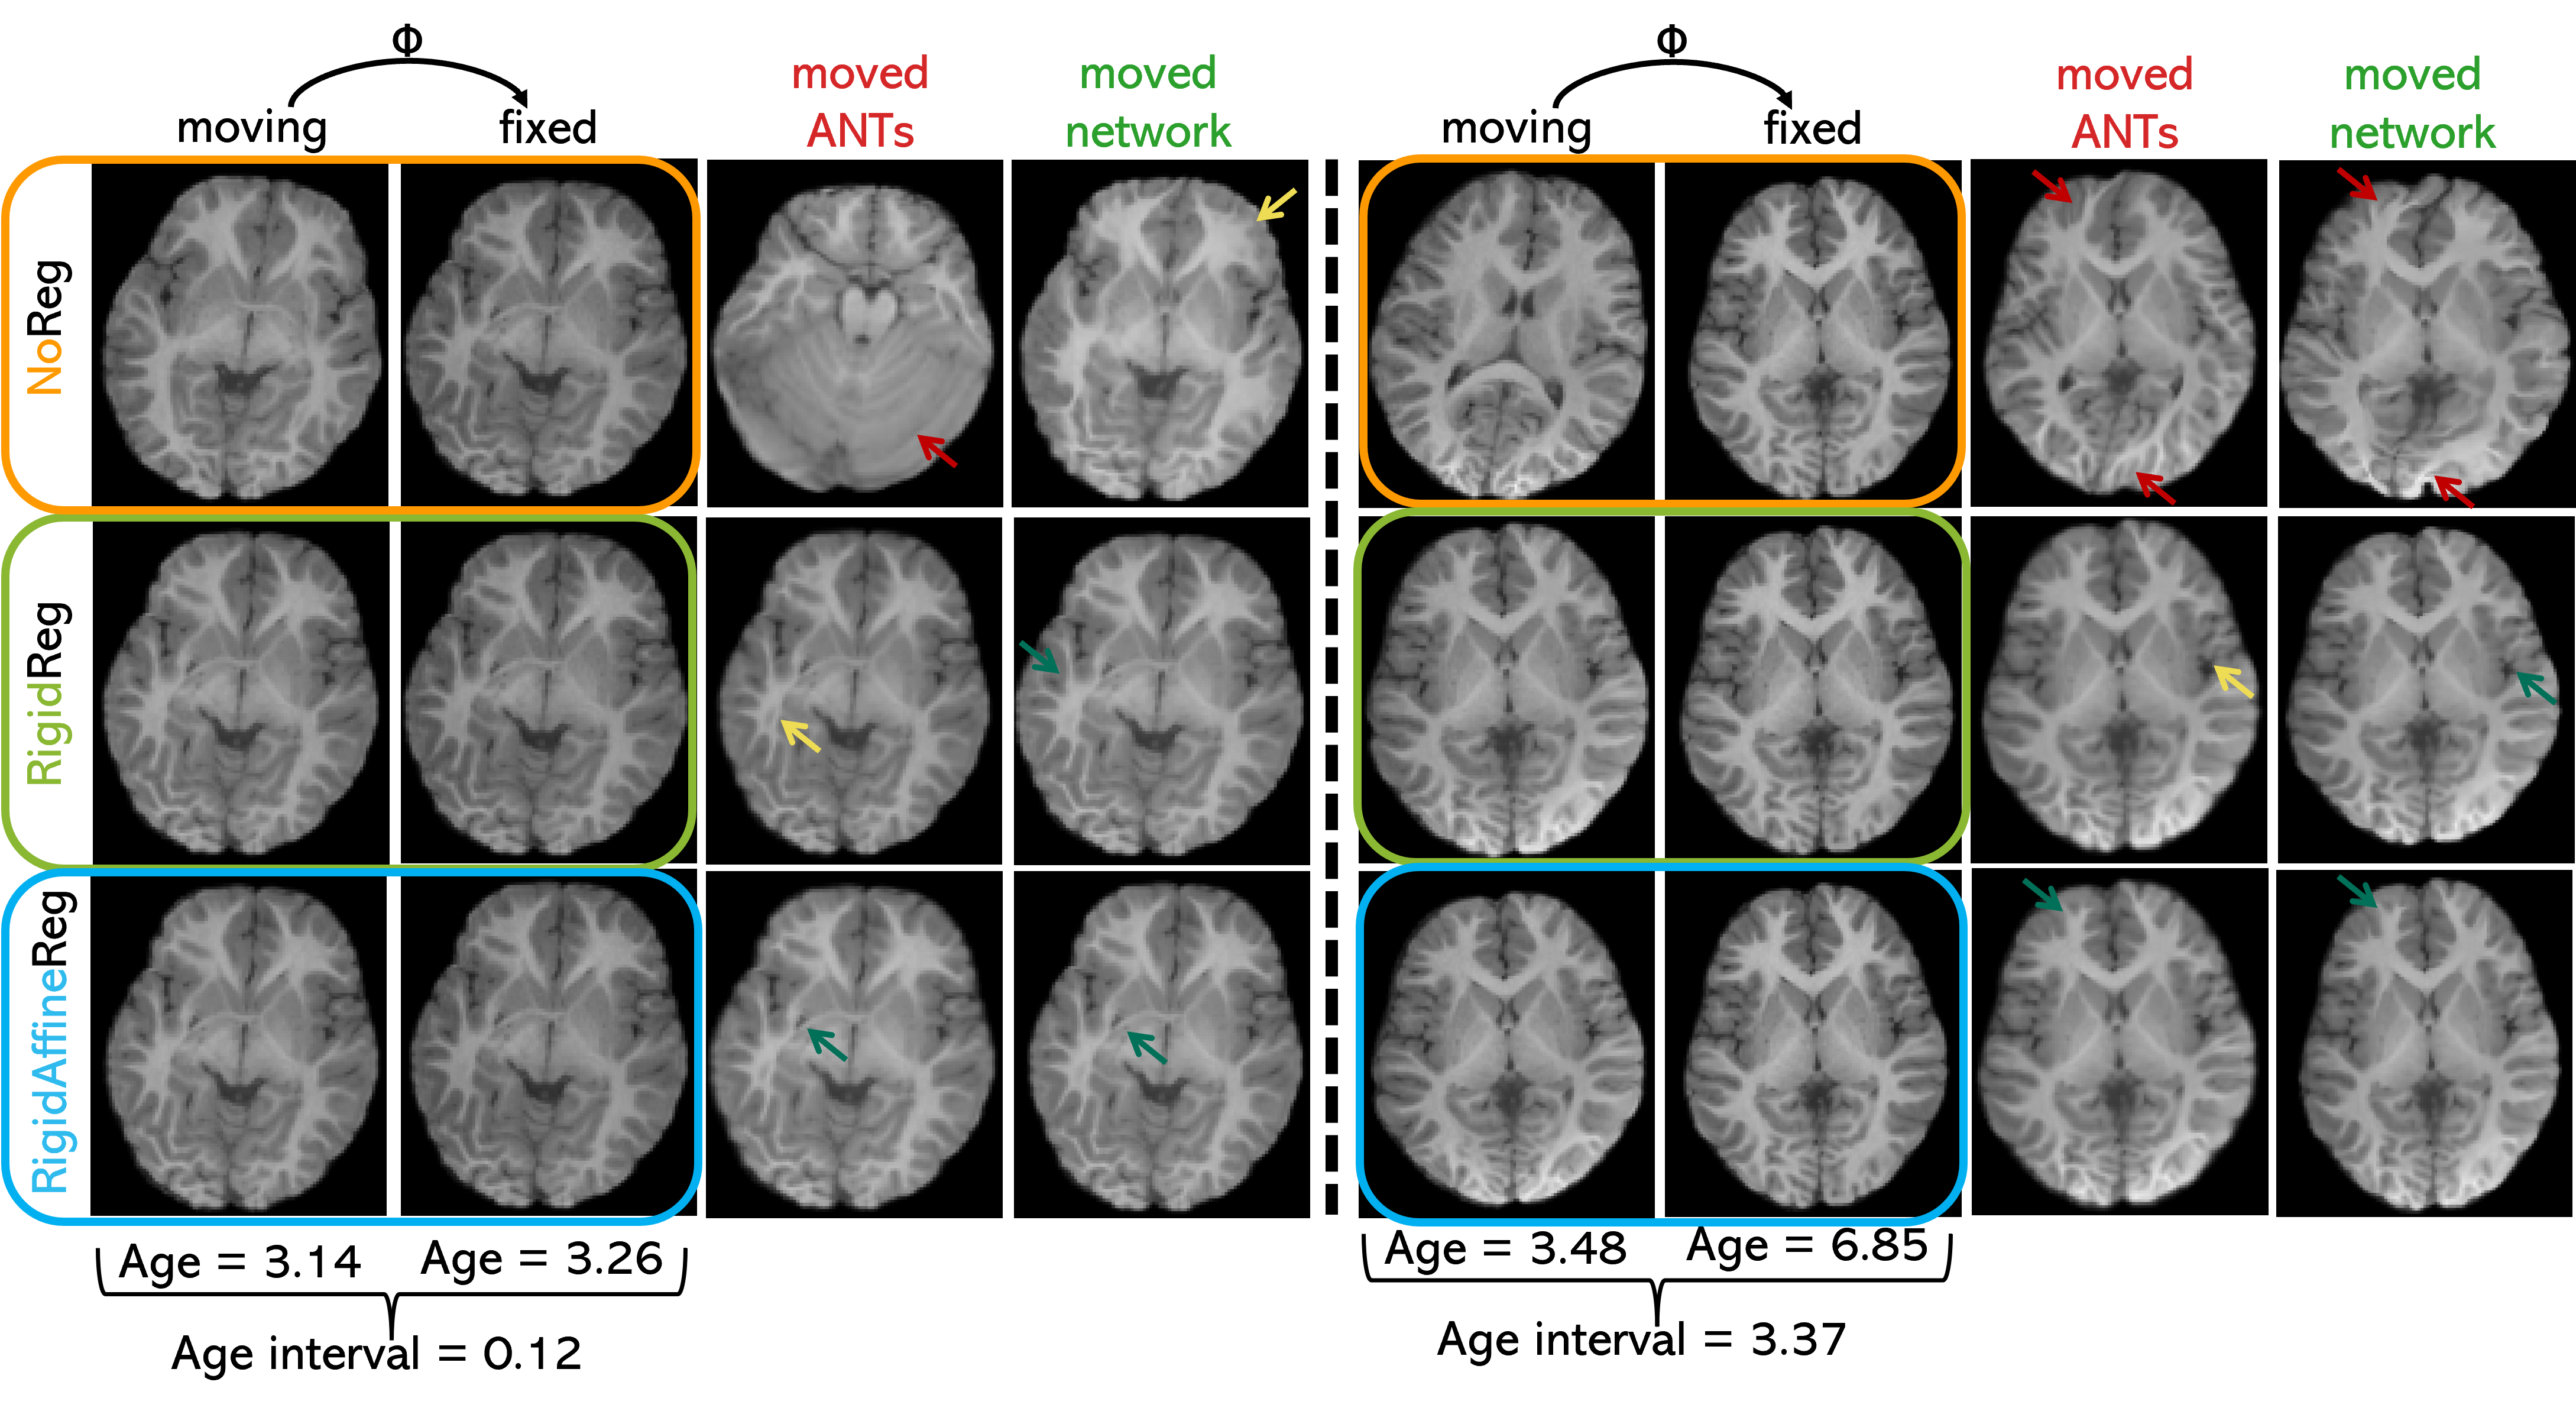

Figure 4 displays an example of registration results on two subjects for all three proposed approaches as well as SyN ANTs counterparts. Moved images are obtained by warping the moving image with the obtained DDFs for both DL-based and SyN ANTs approaches using antsApplyTransforms function from ANTs. Red arrows in the images indicate regions where the warping did not go as expected. On the other hand, green arrows indicate relatively good reproductions of the desired fixed image when inspecting the moved image. Yellow arrows identify areas in proximity to the structures from the fixed image. However, these areas may display blurriness or slight deviations from the expected alignment, indicating regions that are not perfectly matched. For both age intervals, in the RR and RAR scenarios, DL Reg seems to attain similar results as SyN ANTs visually.

Figure 4: Visual representation of the results obtained with all three DL-based approaches ( moved network) compared to SyN ANTs ( moved ANTs) results with an age interval between moving and fixed images of 0.116 years on the left and 3.37 years on the right. Red arrows highlight instances of misalignment, yellow arrows indicate blurriness or minor deviations from the fixed image, and green arrows denote successfully aligned areas.

Dice Scores in Global Tissues: When examining each segmented tissue separately within the smaller set of 18 regions derived from SynthSeg, where WM and CSF each constitute 27.8% of the total regions, and GM makes up the remaining 44.4%, DL Reg using the RAR initialization outperforms RR for WM (0.928±0.016 vs. 0.865±0.021), GM (0.934±0.014 vs. 0.865±0.022) and CSF (0.721±0.037 vs. 0.866±0.030) segmentations. However, CSF Dice scores consistently tend to be lower compared to WM and GM for both DL Reg and SyN ANTs across all three initialization approaches. Our interpretation is that CSF is more susceptible to the effects of minor misregistration, given its predominantly thin structure around the brain, encompassing the CSF and ventricles. In contrast, WM and GM comprise larger, internal structures, such as the brain stem and cerebral white matter within WM, and the cerebellum cortex within GM. These superior results from RAR are to be expected as all global transformations (rotation, translation, shear, and scaling) are accounted for by the rigid and affine registration pre-alignment steps used for RAR. Therefore, as visualized in Figure 4, the RAR method can uncover local modifications on the moved image after passing through the network. Contrary to RAR, NR has difficulties doing both local and global transformations as no initialization was applied. Indeed, as presented in Figure 4, parts of the brain microstructures are an unrealistic warping combining both elements from the moving and fixed images for the example pair with an age interval of 3.37 years. The local transformations are not reproduced as well as when using the two other initialization approaches (RR and RAR). Indeed, as visible on both examples in Figure 4, using only a SyN transformation does also not reproduce smaller microstructures correctly, sometimes completely warping incorrectly (for the lower age interval), as no global transformation is done beforehand.